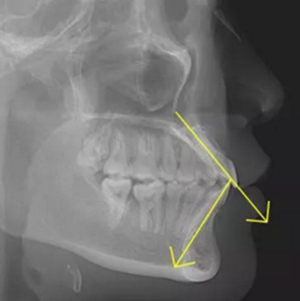

正常情況下,我們的上前牙是蓋在下前牙唇側(cè)3mm內(nèi)的,上下切牙牙軸交角為125°左右,

但前牙閉鎖合是上前牙下垂伸長(zhǎng),內(nèi)扣完全鎖住了下切牙,正面觀時(shí)我們??床坏较虑醒溃虑醒绖t常擁擠伸長(zhǎng)咬到了上腭內(nèi)的牙齦上,上下前牙發(fā)生的交角幾近180°。

正常前牙交角

前牙閉鎖合交角